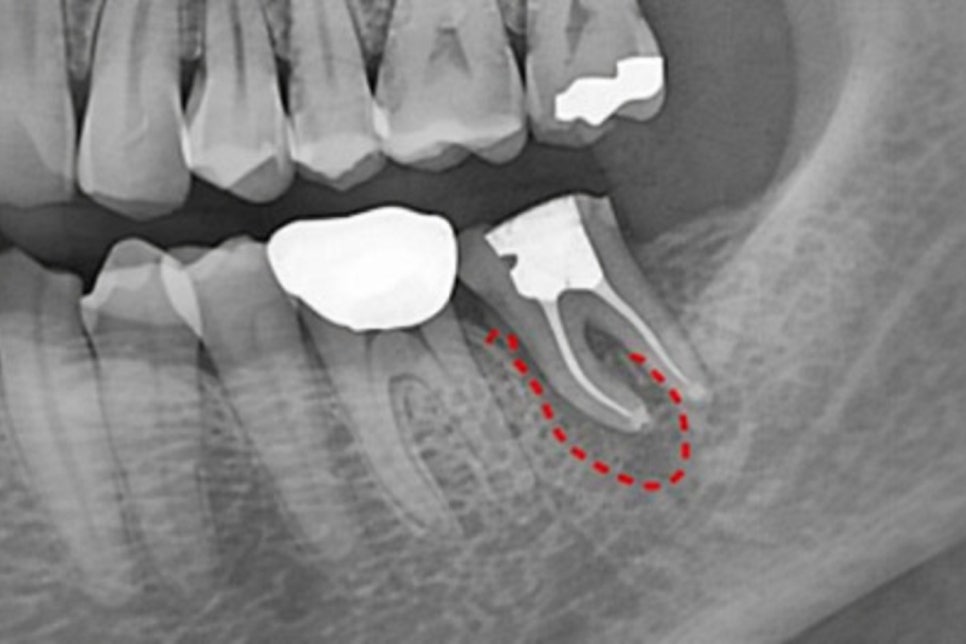

주로 뿌리 끝에 심한 염증이 생겨

고름이 차거나 얼굴이 붓는 상황,

또는 이전에 신경치료를 받은 곳에서

재감염이 발생했을 때 고려해볼 수 있습니다.

특히 어금니처럼 뿌리가 깊고

복잡하게 자리를 잡은 경우에는

구강 안에서의 접근만으로

염증을 완전히 제거하기 어려울 수 있습니다.

근관 내부가 석회화되어 기구 삽입 자체가

불가능할 때에도 마찬가지입니다.